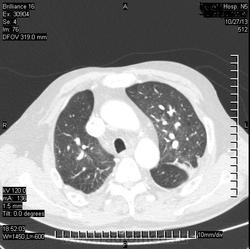

Коллега, а что, инфаркт искали? Или у Вас так окклюзии ЛА ищут? Интересно, а просто ОГК , для искл. пневмонии

( или инфаркт-пневмонии) слева?

Виноват. Не все вчера успел выложить.ТЭЛА.

Всё понятно стало. А, вот мне, как-то не очень легочная вена слева... Там все нормально? Или тоже тромб?

ТЭЛА слева, я правильно вижу?

Да. Слева.

Я не маститый "КТ-шник". На дежурствах в 2-3 часа ночи главное ухватить суть (на мой взгляд). Может быть тромб.